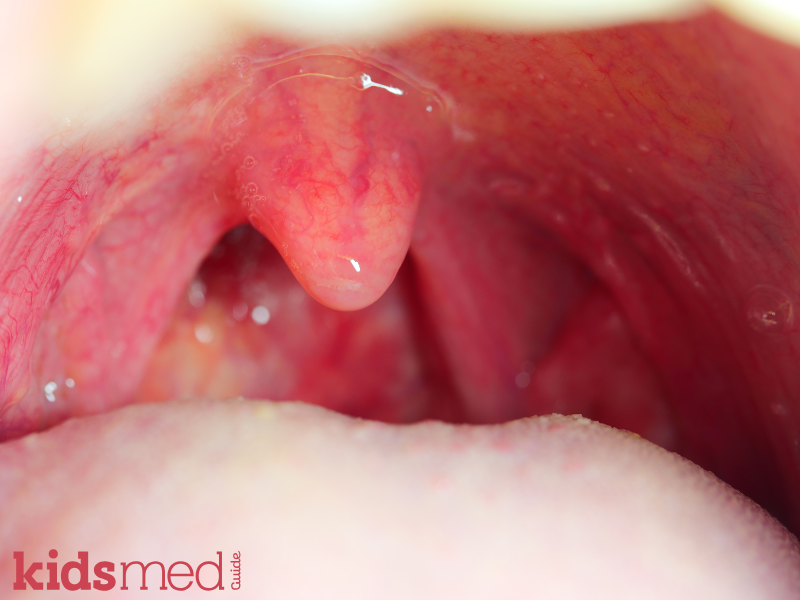

It is caused by Group A Streptococcus bacteria (GAS), also known as Streptococcus pyogenes. It typically presents as acute pharyngotonsillitis, a fancy medical term for "crazy painful red swollen throat" caused by inflammation of the throat and tonsils. However, strep throat can sometimes be sneaky and have other symptoms, like rash, stomach aches, vomiting, or headache.

- Dark red/purplish colored spots or white patches on and around the tonsils